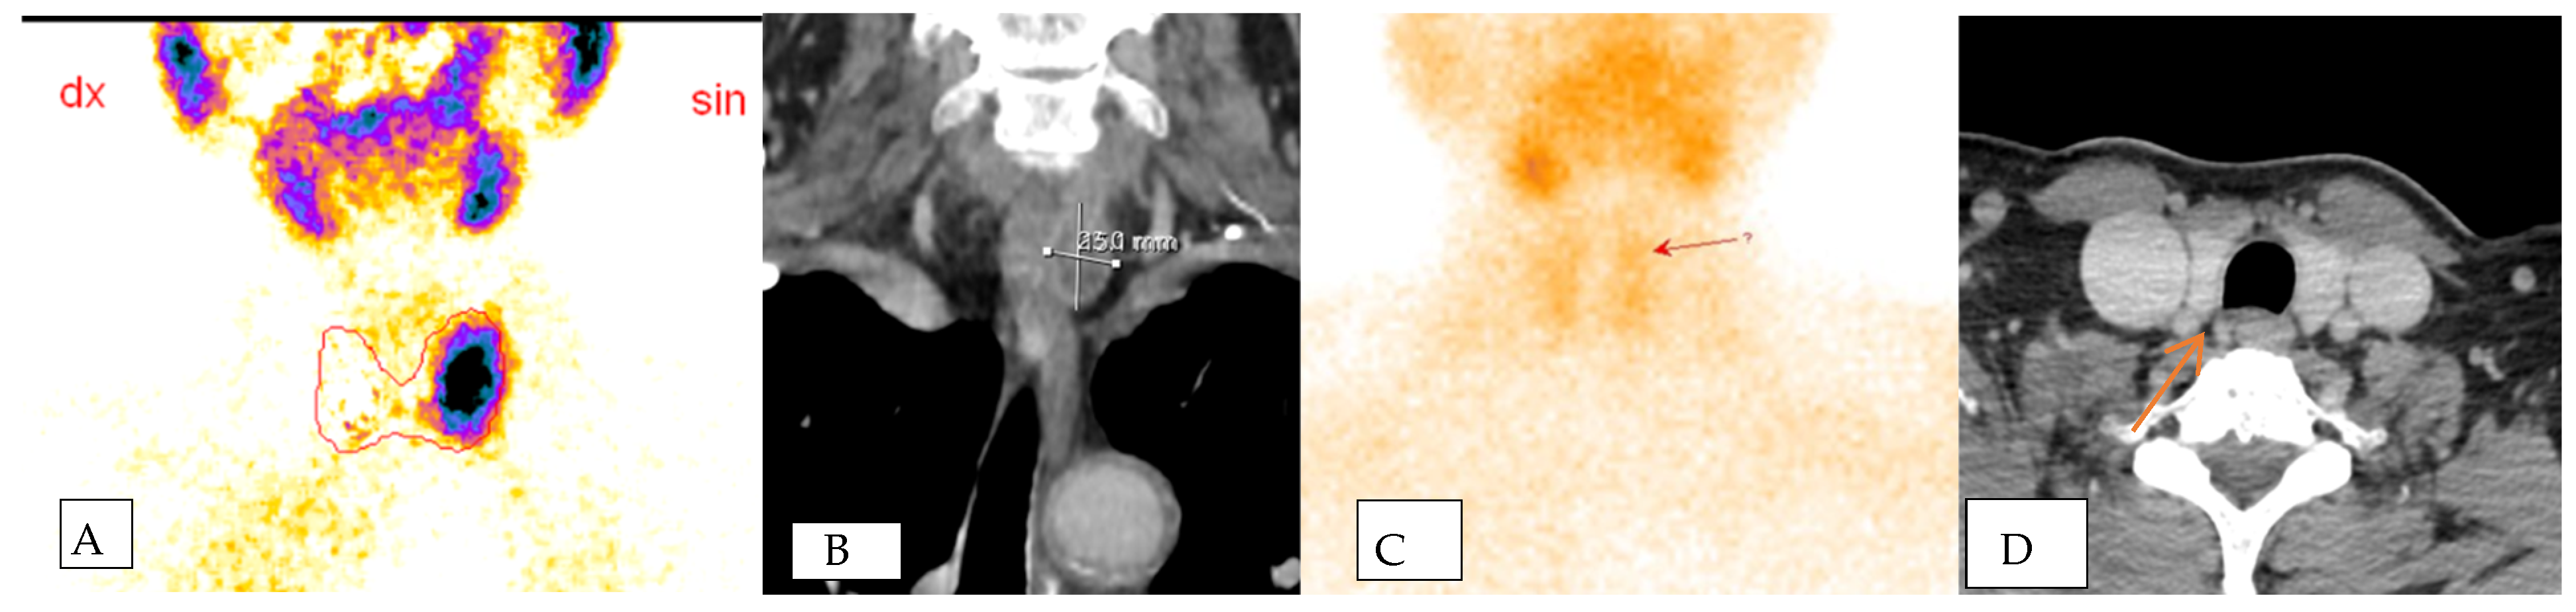

The localization of parathyroid adenomas, a crucial aspect of our investigation, yielded distinct results. Among the non-invasive radiological diagnostic methods employed, ultrasound (US) correctly identified the localization in 10 out of 22 cases (45.45%), computed tomography (CT) in 6 out of 22 cases (27.27%), and scintigraphy in 9 out of 22 cases (40.9%). However, the standout performance was attributed to SVS, which demonstrated superior accuracy in precisely lateralizing the adenoma, correctly identifying it in 15 out of 22 cases (68.18%). This emphasizes SVS as the most accurate preoperative method for determining adenoma lateralization (Figure 1).

Delving into the SVS results, seven patients showed negative findings. Among these, two did not have clinically proven parathyroid adenomas, while five had false-negative SVS results but were later confirmed to have adenomas intraoperatively. This highlights the dual role of SVS, not only in identifying pathological glands accurately, but also in contributing to the precision of preoperative diagnoses. When SVS correctly lateralized the pathological gland, the PTH gradient was observed to be 1.5–2 times higher than the normal PTH level, providing valuable guidance for localizing the adenoma within the specific anatomical quadrant of the neck (Figure 2).

In terms of blood and urine tests, preoperative calcium (Ca) levels showed a positive statistically significant correlation with preoperative PTH levels (r = 0.403, p = 0.033), indicating that higher PTH levels were associated with higher Ca levels. However, there was no statistically significant correlation between preoperative Ca levels and phosphorus (P) levels in the blood or the P/Ca ratio in urine (Figure 1).

Figure 1. Assessment of Adenoma Localization and Lateralization Methods. Presenting the effectiveness of diverse imaging modalities in both localizing and lateralizing parathyroid adenomas. The data are portrayed as percentages, illustrating the precision of identification for each method and is grounded in a total of 22 cases.